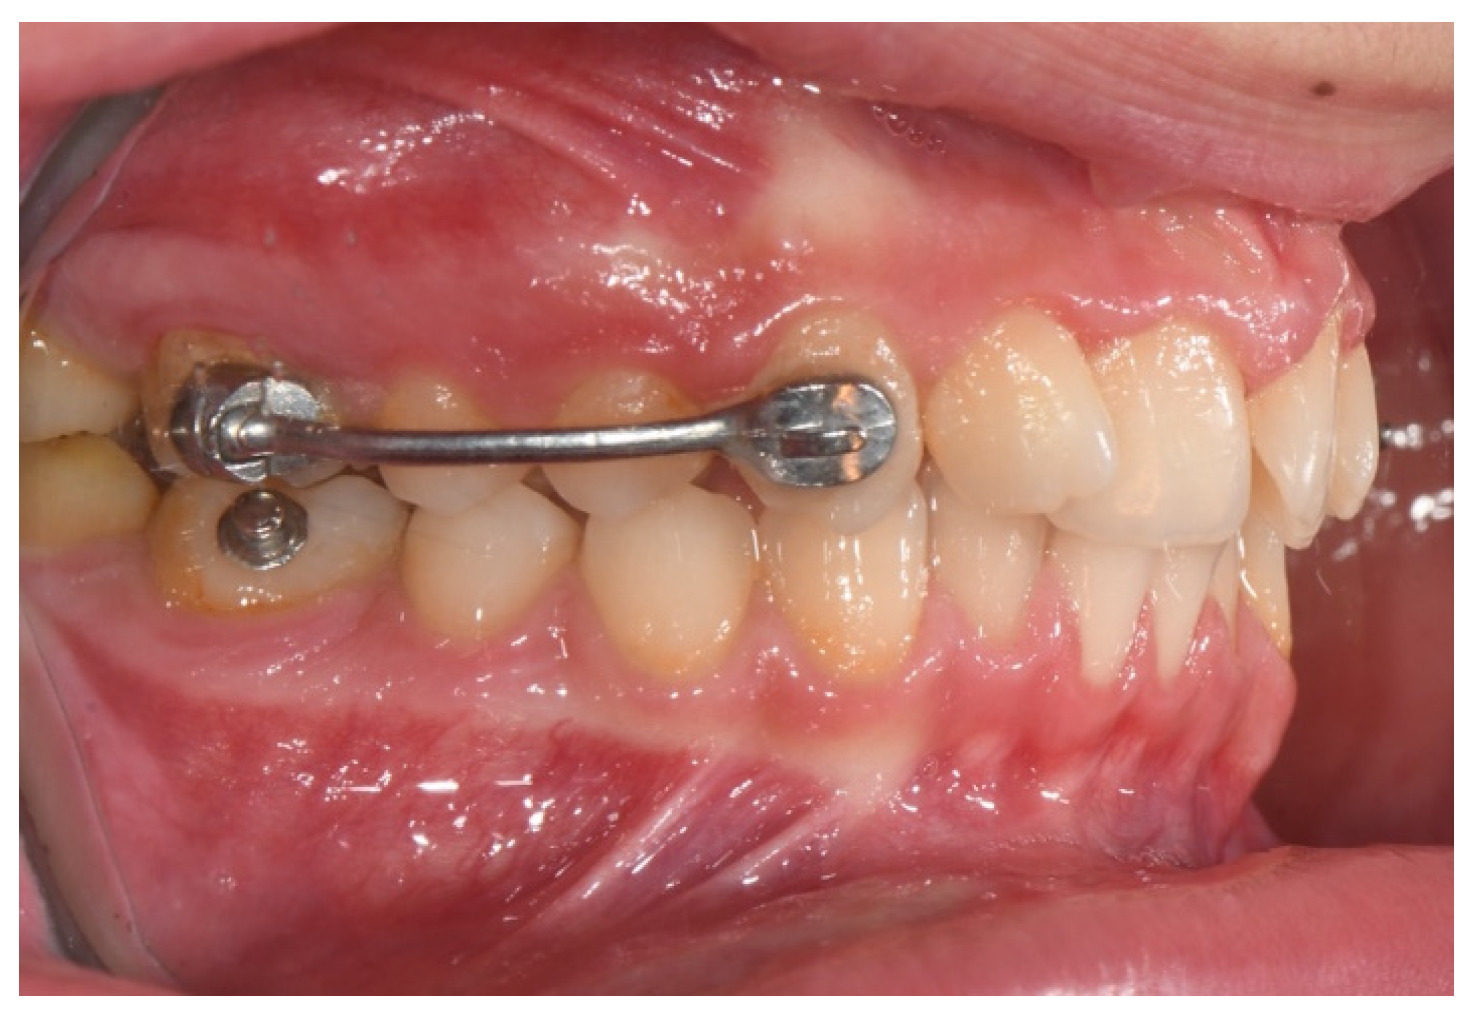

4.1.11. Carriere Distalizer

- Yin, K.; Han, E.; Guo, J.; Yasumura, T.; Grauer, D.; Sameshima, G. Evaluating the treatment effectiveness and efficiency of Carriere Distalizer: A cephalometric and study model comparison of Class II appliances. Prog. Orthod. 2019, 20, 24. [Google Scholar] [CrossRef]